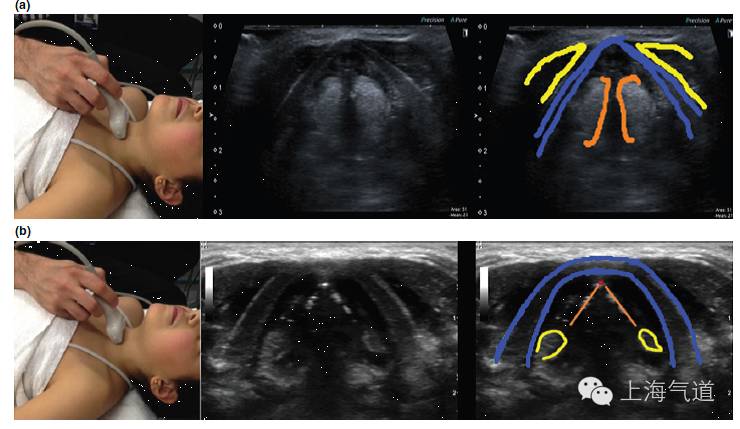

图1a. 将探头置于假声带水平取横断面超声影像,图中标识F为高回声的脂肪;M为低回声的肌肉组织,暗区内可见高亮的筋膜结构;C为低回声的软骨结构,其超声影像因其钙化程度而有差异,总体来说,回声较其周边的脂肪组织低。b.将探头置于右颈部取纵切面,CA为线性管状的颈动脉,其内为无回声的血液;V为颈椎椎体,超声很难穿过骨性结构,因此会在其表面形成高亮的反折线,其下形成伪影

图2a. 将探头置于颏下区取横断面,绿色区域为舌体,红色为口腔内肌肉组织,蓝色为下颌骨及其伪影。b.将探头旋转90度并置于中线位置,取此区域的长轴影像

图3 a. 探头置于下颌骨水平取纵断面,黄色为颌下腺,红色为颈外动脉,棕色为扁桃体。b. 将探头旋转90度所得此区域的影像

图4a. 假声带水平横截面显示,黄色为带状肌,蓝色为甲状软骨,橙色为假声带。b.将探头轻微向尾端移动至真声带水平,蓝色为甲状软骨,橙色为真声带,红色为前联合,黄色为杓状软骨